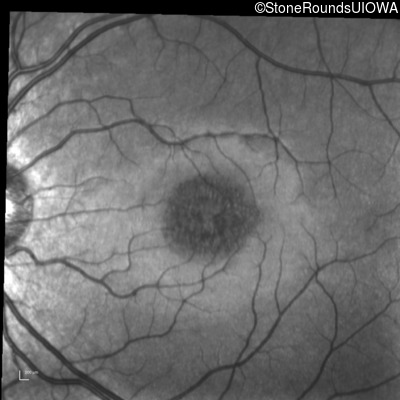

Infrared Fundus Photograph - Right - 20/50 +2 sc

Exemplar